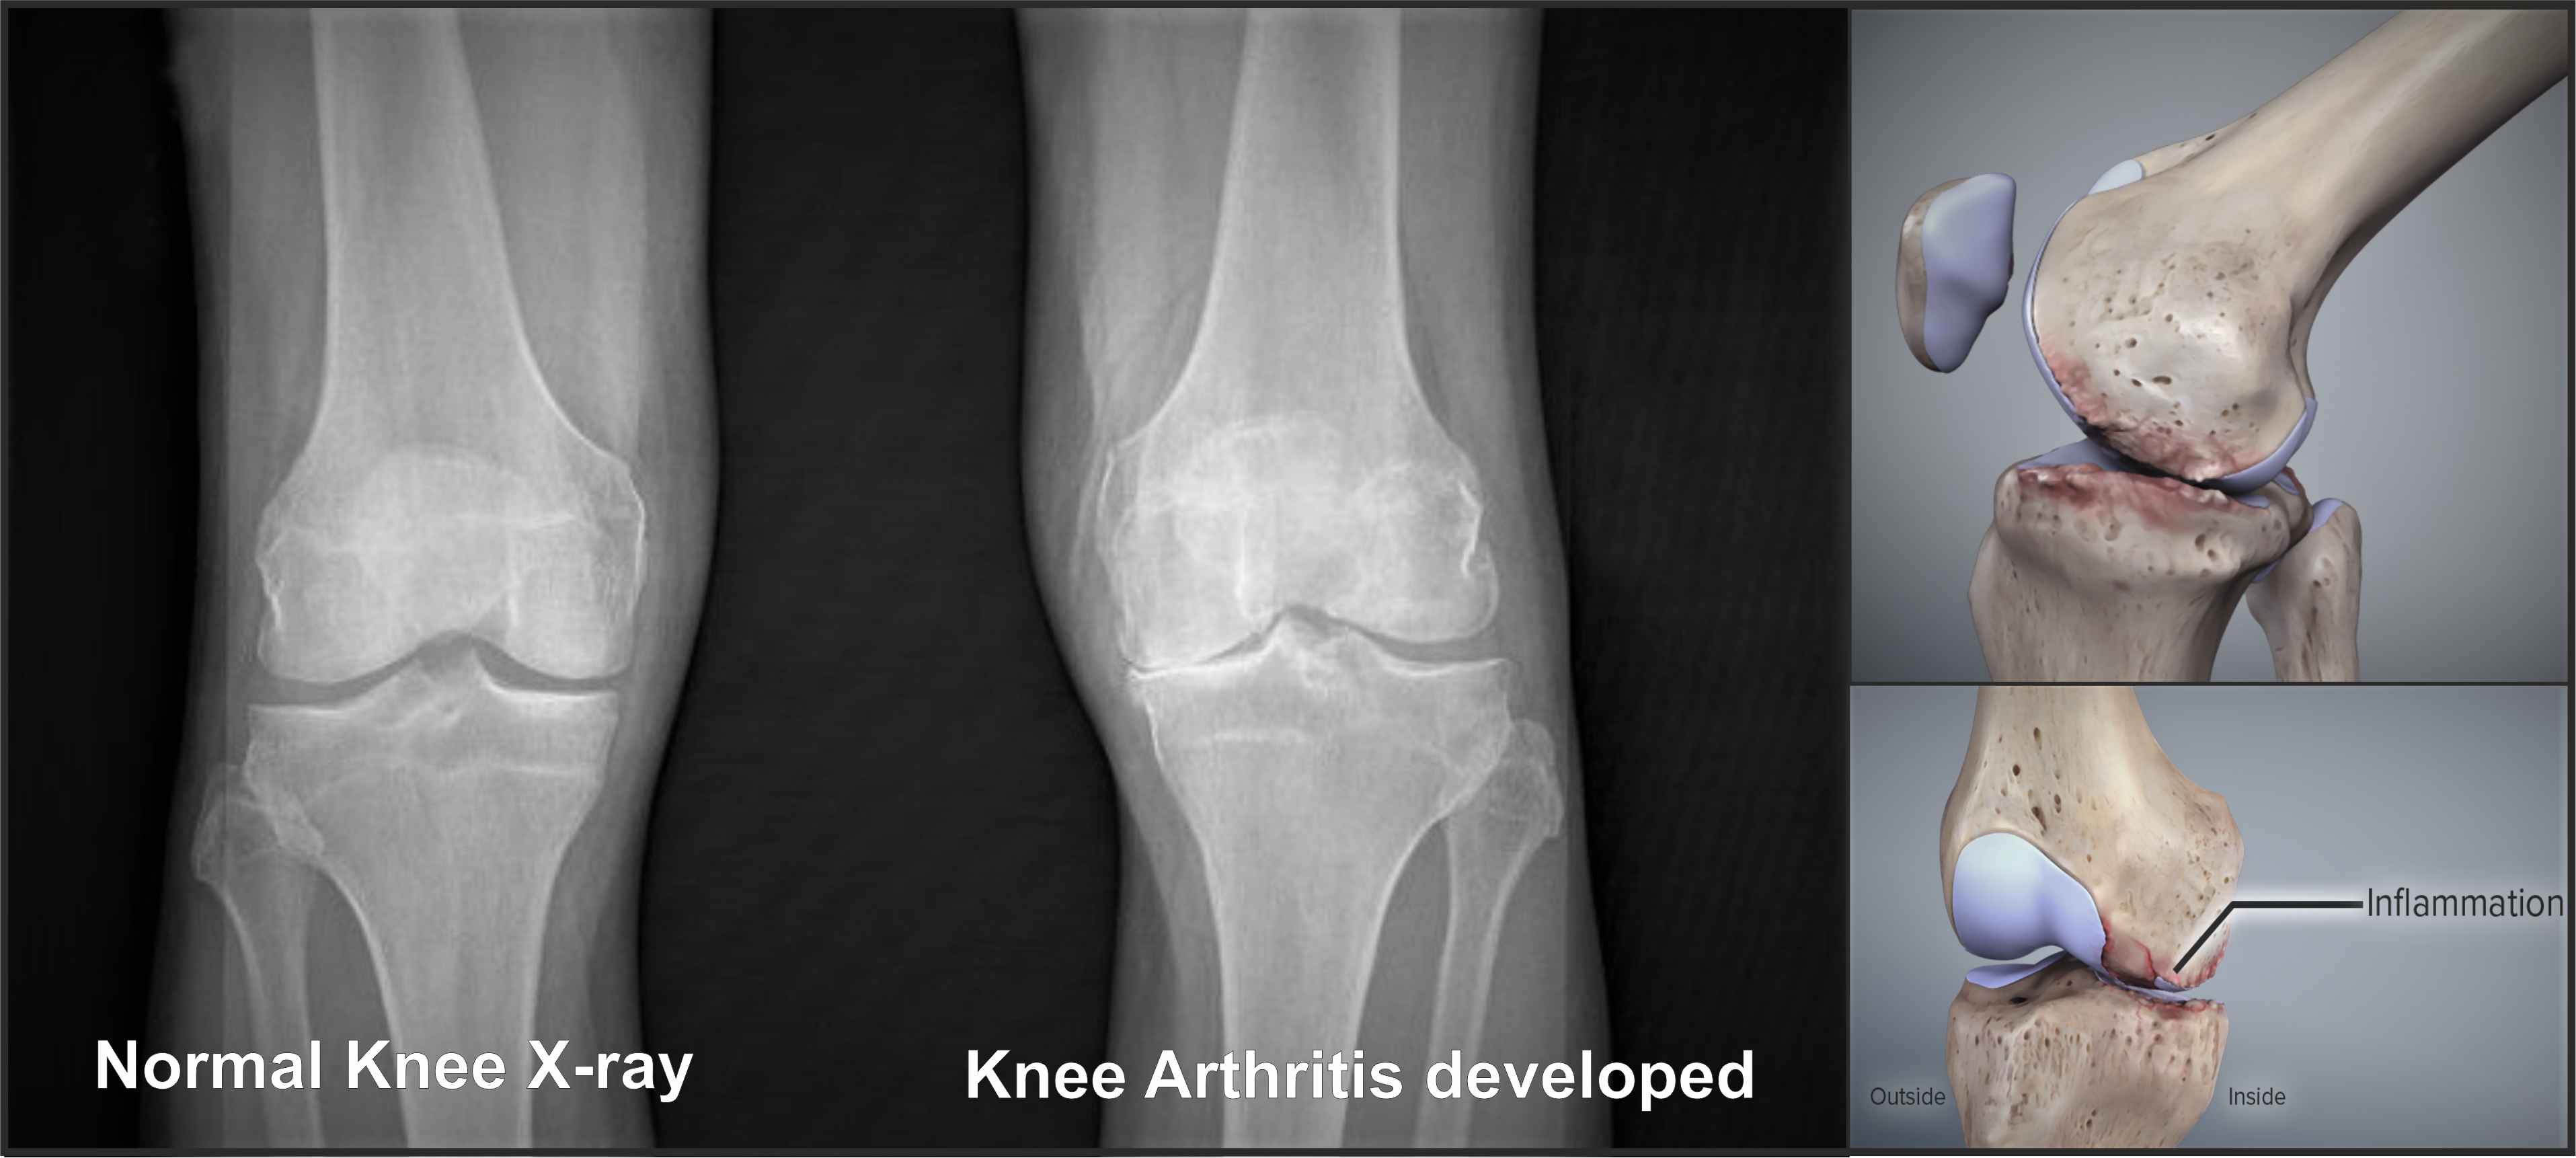

Exact reason is not known. Stress on articular cartilage and bone leads to wear and tear to these structures. Joint inflammation is very minimum compare to other arthritis and seen mostly in advanced disease.

Pain around the joint that increases with weight bearing and movement and improves with rest. It may be associated with morning stiffness and swelling of the joints. Clinical signs are tenderness, crepitus, joint effusion, decreased range of movement,etc. X-ray shows decreased joint space, osteophytes formation and osteoporosis of bone.